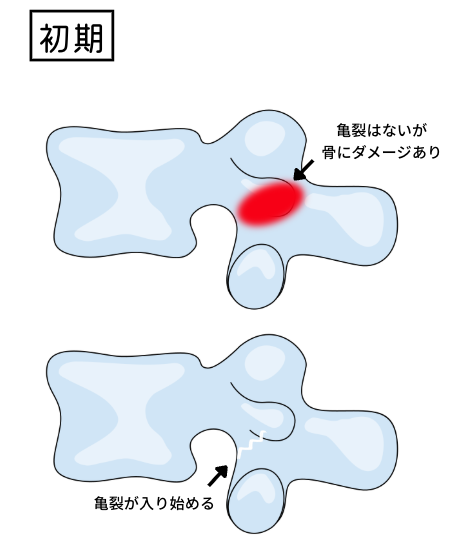

また、分離症は成長期特有の怪我といえます。成長期の骨はまだ硬さが十分ではありません。そのため、スポーツ時に腰の骨同士のぶつかり合いが繰り返されることで、骨に少しずつダメージを与え徐々に亀裂が発生してしまうというわけです。

ステージ1の「初期」では、骨に炎症が見られたり、実際に亀裂が入り始める時期です。安静期間は1ヶ月〜3ヶ月ほどが多い印象。少なくとも骨の炎症が治ったり、亀裂がなくならなければスポーツ復帰できません。